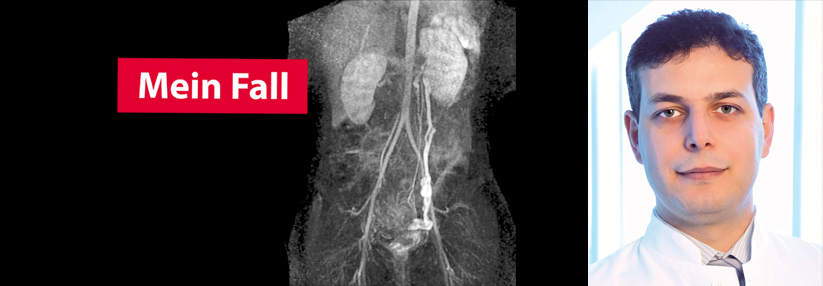

Nussknackersyndrom Verklemmte Nierenvene sorgt für Blut im Urin

Ein zwölfjähriger Junge kam aufgrund einer rezidivierenden Makrohämaturie mit Koagelbildung und linksseitigen Flankenschmerzen in die Kinder­urologie. Mittels Computertomografie hatte man andernorts eine Urolithiasis bereits ausgeschlossen, berichten Dr. ­Alexander ­Cox vom Uniklinikum Bonn und ­Kollegen.

Die erneute Anamnese ergab keinerlei Hinweise auf Trauma, Infektion, Diarrhö, Gerinnungsstörungen, Manipulation oder Medikamenteneinnahme als Ursache. Nach eigenen Angaben sprang der junge Patient leidenschaftlich gerne Trampolin und hatte im Vorfeld einen deutlichen Wachstumsschub durchgemacht. Bei der körperlichen Untersuchung wurden keine auffälligen Befunde gestellt. Der Junge war von schlanker Statur, es lagen weder Ödeme noch ein arterieller Hypertonus vor. Nach umfangreichen laborchemischen und bildgebenden Untersuchungen wurde die Diagnose Nussknackersyndrom gestellt. Eine konservative Therapie sowie der Verzicht auf den auslösenden Sport erwiesen sich rasch als erfolgreich.

Darüber hinaus kann die Schnittbildgebung mittels Magnetresonanz- oder Computertomografie weitere Anhaltspunkte liefern. Dies trifft allerdings nur zu, sofern in den axialen und koronaren Aufnahmen eine Darstellung der Venenkompression bzw. des Abgangswinkel der A. mesenterica superior sowie der sekundären Genesen gelingt. Der Grenzwert für das Verhältnis der Diameter liegt bei 4,9:1. Der Verdacht auf ein Nussknackersyndrom erhärtet sich außerdem, wenn der aorto-mesenteriale Abgangswinkel der A. mesenterica superior < 35° beträgt.